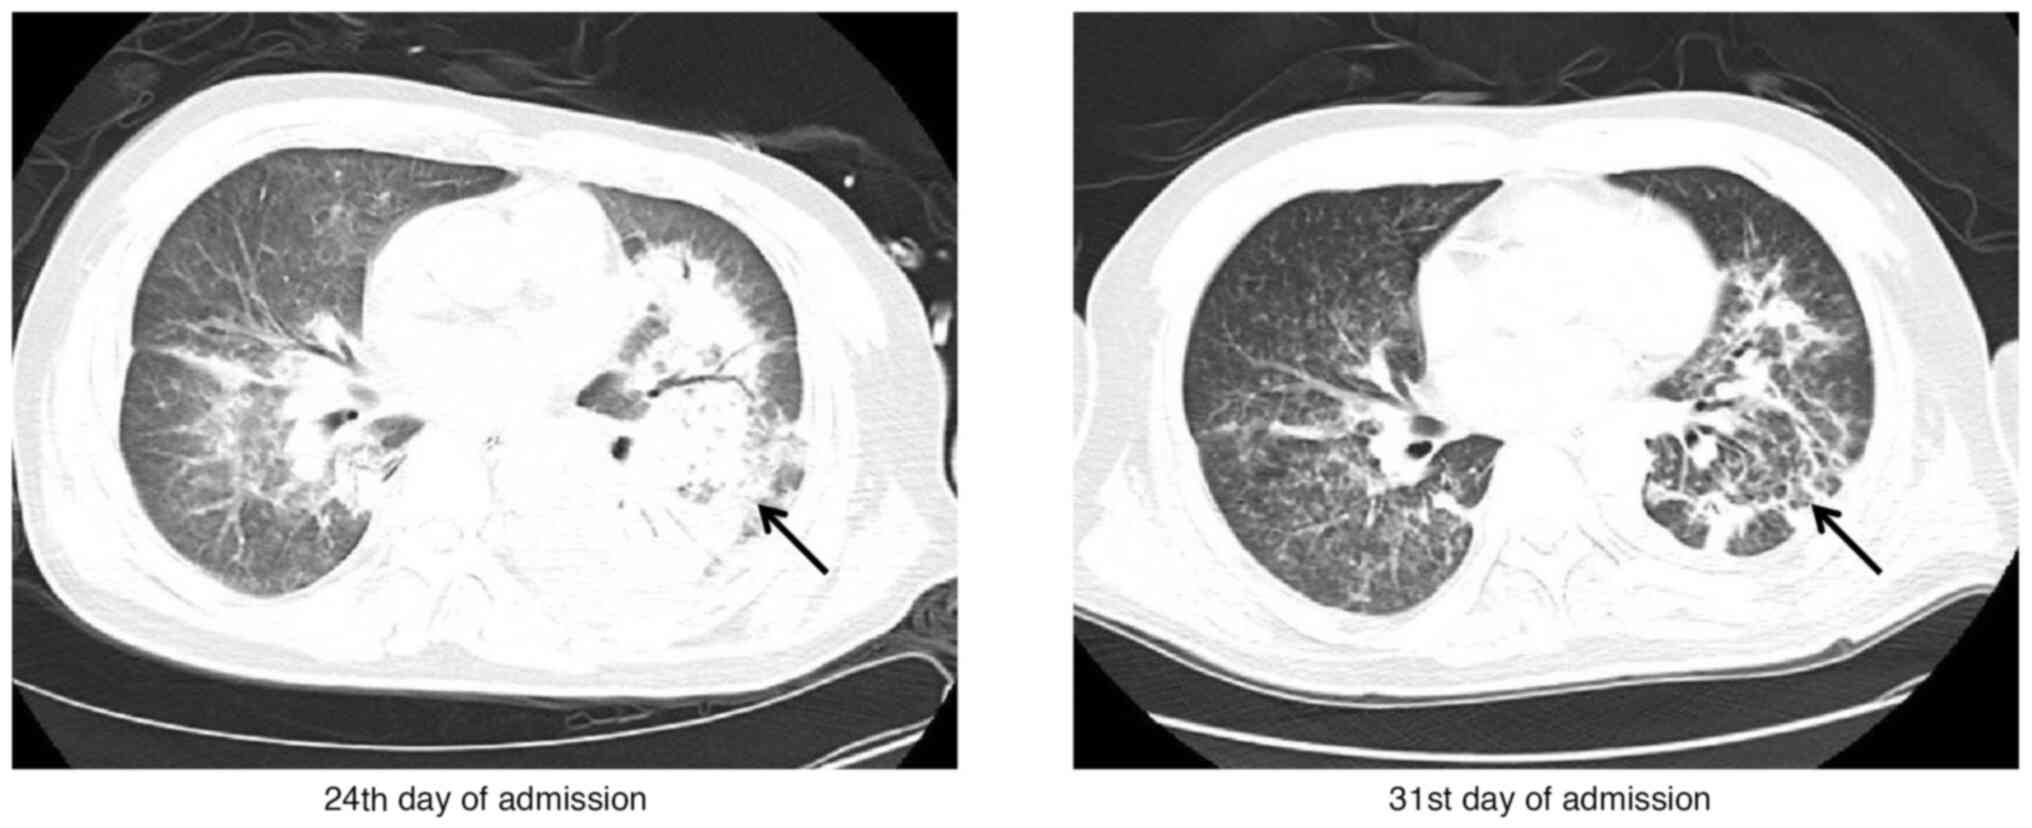

Hospital‑acquired pneumonia caused by Kodamaea ohmeri during extracorporeal membrane oxygenation treatment: A case report and literature review

Kodamaea ohmeri (K. ohmeri) is an ascosporogenic species of yeast that belongs to the genus Ascosporogenous and the family of Saccharomycetaceae. It has recently been found to cause various types of infections, particularly in critically ill immunocompromised patients. The present study describes a case of hospital‑acquired pneumonia caused by K. ohmeri during veno‑arterial extracorporeal membrane oxygenation. The fungal culture turned negative after the administration of caspofungin and amphotericin B. Extracorporeal membrane oxygenation (ECMO) is an adjunctive medical technique that provides temporary cardiopulmonary support for patients. Previous observations have suggested that the immune function of patients will typically decline during the use of ECMO, rendering infection to be one of the main complications of ECMO. K. ohmeri is a rare pathogenic fungus, particularly in immunocompromised individuals with vascular catheters, while amphotericin B is the most common antifungal therapy administered to treat K. ohmeri infections. It is important to raise awareness of rare fungal infections and actively treat them.